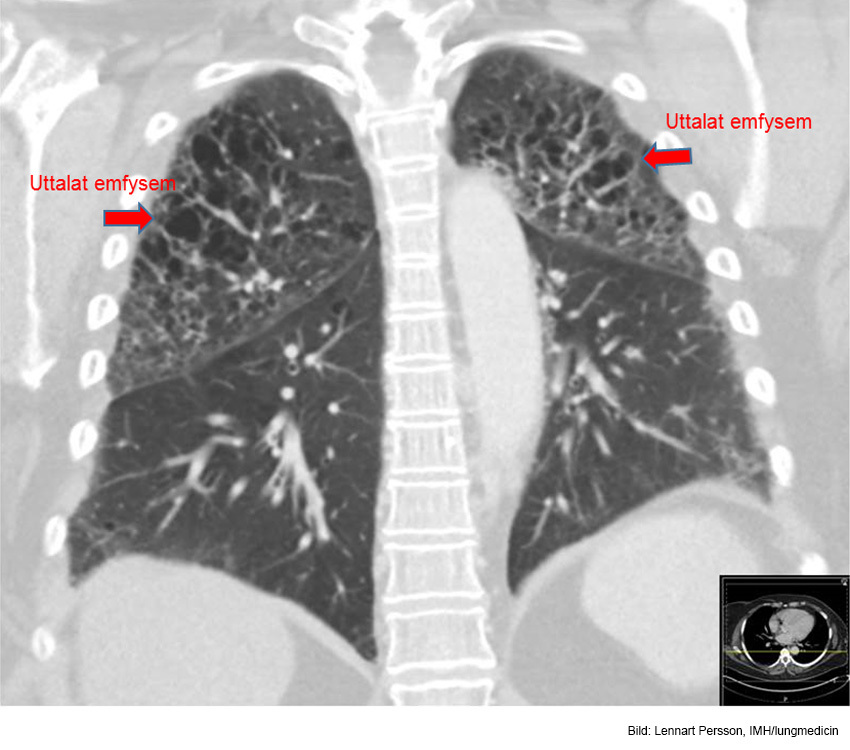

Vad ser du här?

Uttalat emfysem inom bägge ovanlober. Basalt ventralt i höger lunga finns en liten tumörmisstänkt förändring.